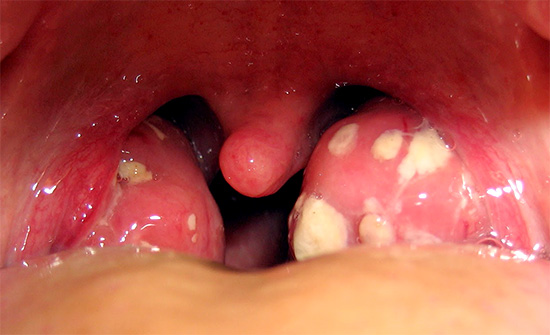

Боль в горле у пациента с классическим случаем ангины.